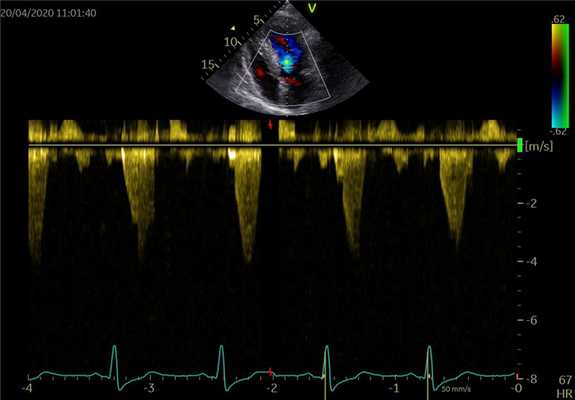

Допплеровская ЭхоКГ очень полезно для оценки функции протезного клапана:

- Препятствие кровотоку. Из-за того, что материал этих клапанов не соответствует требованиям, скорость потока через них отличается от обычных стандартных клапанов (см. Таблицу 6.1). Большинство протезов клапанов создают препятствия для кровотока. Можно произвести ряд измерений:

- Пиковая скорость. Она выше, чем в обычных клапанах, из-за относительно меньшей площади отверстия, обусловленной большим объемом искусственного материала. Пример диапазона приведены в таблице. Как правило, пиковая скорость> 2 м/с в МК обычно указывает на дисфункцию как механических, так и биологических протезных клапанов. Скорость потока в протезе аорты обычно

- Градиент давления (ΔP). Этот показатель рассчитывается по упрощенному уравнению Бернулли (ΔP = 4V2).

- Площадь отверстия клапана - измеряется по уравнению непрерывности

ТАБЛИЦА Скорость потока (м/с) через некоторые нормально функционирующие механические и тканевые протезные клапаны

Клапан Митральный Аортальный Шар и клетка Старр - Эдвардс 1,4-2,2 2,6-3,0 Поворотно-дисковый (один диск) Björk-Shiley 1,3-1,8 1,9-2,9 Двустворчатый St Jude 1,2-1,8 2,3-2,8 Свиной биологический Carpentier-Edwards 1,5-2,0 1,9-2,8 Разные эхолаборатории имеют разные диапазоны. В индивидуальном случае более важно изменение скорости от послеоперационных значений.